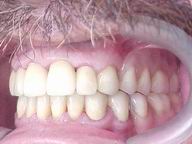

Reabilitação funcional e estética em ambas as arcadas

com próteses fixas e removíveis de encaixe de precisão.

DEPOIS

Vista Lateral Direita

Vista Lateral Esquerda